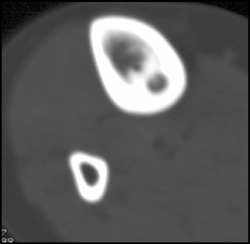

Diagnosis

Fracture